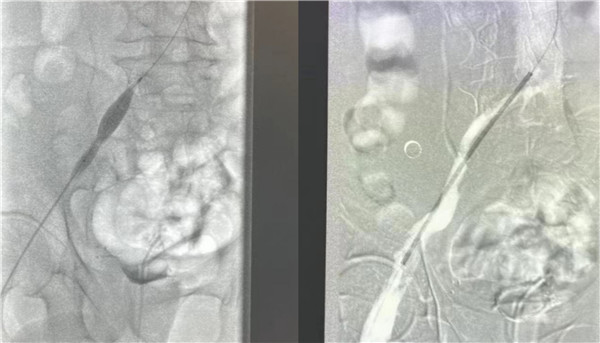

高大爷入院后立刻开启绿色通道,普外科血管介入团队放弃假期休息,当天急诊为他进行了介入手术治疗。为了防止肺栓塞的发生,首先为高大爷进行下腔静脉滤器的植入,与此同时造影显示患者左下肢血管内布满血栓,使用AcoStream血栓抽吸系统为患者清除血管内的血栓,高大爷还存在左侧“髂静脉压迫综合征”立刻完善方案,为他进行球囊扩张,支架植入,在保证患者的安全前提下,采用“一站式”解决方案,一次性为高大爷从病根上解决诱发血栓的原因并治疗了血栓,即刻效果显著,高大爷下肢大腿腿围术前43厘米,术后即刻41.5厘米,术后第一天41厘米,小腿腿围术前34厘米,术后即刻32厘米,术后第一天31厘米。同时也避免可能的PTS发生。介入手术创伤小,仅有一个穿刺点,患者术后恢复快,大大的提高了患者的就医感受,并且为患者节省了费用。

下肢深静脉血栓患者术前造影

球囊扩张

术后